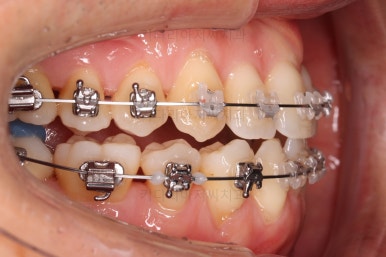

화살표는 사랑니인데요. 이 분의 경우 아래 앞니가 1개 없고, 1개를 추가로 뽑아서 윗니 대비 아랫니가 총 2개 모자란거죠.

운이 좋게도 이 분은 사랑니까지 잘 나와있던 상태라 내버려두기 아까워 함께 가지런하게 해주고 사용하실 수 있게 해드렸어요.

좀 더 마무리를 하고 치료 종료하기로 했어요.

부산비수술교정 키다리아저씨치과에서 시행한 이번 치료의 결과입니다.

아랫니 갯수가 모자라고 중앙이 맞지 않았고 짝이 안맞는 상황이었으나 비교적 잘 마무리를 했어요.

거꾸로 물리는 상황이 개선되었기 때문에 앞니나 어금니의 교합은 이전과 비교할 수 없을만큼 좋아졌지요.